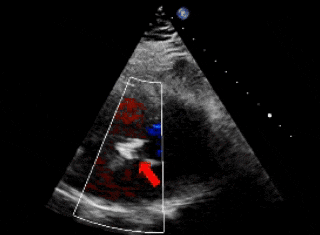

术前超声

超声下可见左盘面贴靠主动脉侧

超声下可见双盘面骑跨